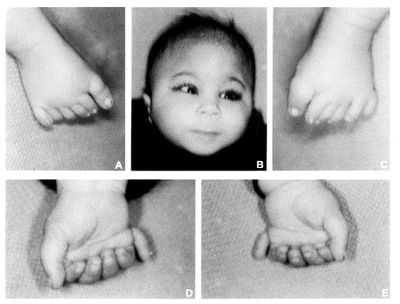

- Неправильное строение рук

Пальцы больных постоянно находятся в напряжении и сжаты. Большой палец больные накладывают поверх остальных. На дефекты рук влияет также и деформация шейного отдела позвоночника, зачастую он аномально укорочен. В медицине встречались случаи, когда детей с хромосомным нарушением присутствовали лишние пальцы.

- Пальцы ребенка сжаты в кулак, возможны лишние пальцы

Полидактилия (лишний палец) у ребенка с синдромом Патау

Полидактилия (лишний палец) у ребенка с синдромом ПатауЭта проблема возникает из-за искажения строения позвоночника, у больных детей он часто бывает укороченным. Руки всегда напряжены и сжаты в кулак. Достаточно редко, но были зафиксированы случаи рождения детей с аномалией количества пальцев.

- Патология затрагивает не только кости черепа, но и другие структуры скелета. Например, у детей с синдромом Патау часто наблюдается полидактилия (появление дополнительных пальцев на стопах и кистях) и синдактилия (сращение пальцев).

Полидактилия (лишний палец) у ребенка с синдромом Патау

- Полидактилия

- Признаки поражения костей, суставов, мышц: сжатая в кулак кисть, полидактилия, сращение пальцев, деформированная стопа.